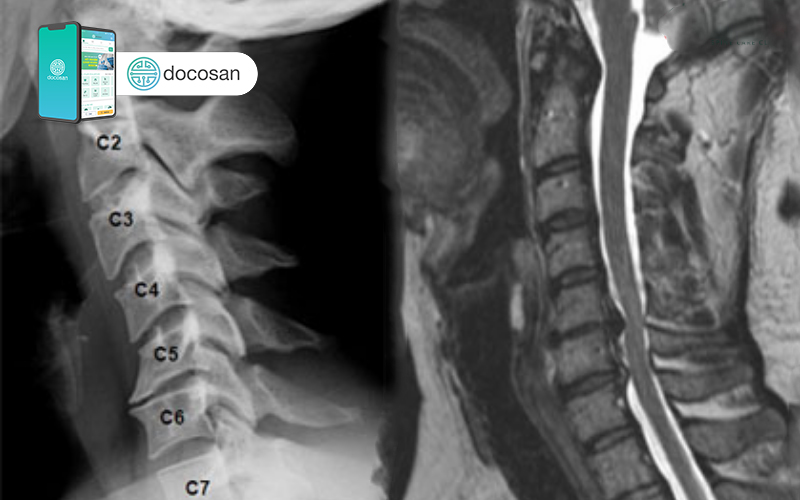

Thoái hóa đốt sống cổ (Cervical spondylosis) là một bệnh lý mãn tính về xương khớp khá phổ biến, tiến triển chậm, thường gặp ở người cao tuổi hoặc những người có tư thế vận động tác động xấu lên cột sống cổ. Bệnh sẽ ảnh hưởng trực tiếp đến các khớp, đĩa đệm của đốt sống cổ. Thoái hoá cột sống cổ có thể gặp ở bất kỳ đoạn nào của đốt sống cổ, tuy nhiên thường gặp nhất là đốt sống C5, C6 và C7.

Nếu nghi ngờ người bệnh bị thoái hóa đốt sống cổ, các bác sĩ có thể yêu cầu xét nghiệm hình ảnh và kiểm tra chức năng thần kinh. Một số phương pháp xét nghiệm hình ảnh bao gồm:

- Chụp X-quang

- Chụp CT

- Chụp MRI